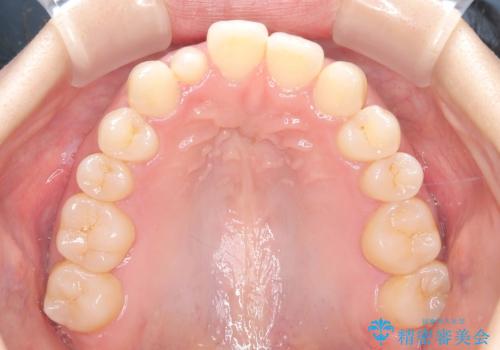

- 歯のデコボコと右上2番の歯の形が気になることを主訴に来院された患者様です。

軽度の叢生(凸凹)であったため、インビザラインのライトパッケージを用いて歯並びを改善しました。その後、右上2番はオールセラミッククラウンにより形態を回復し、審美性を向上させました。